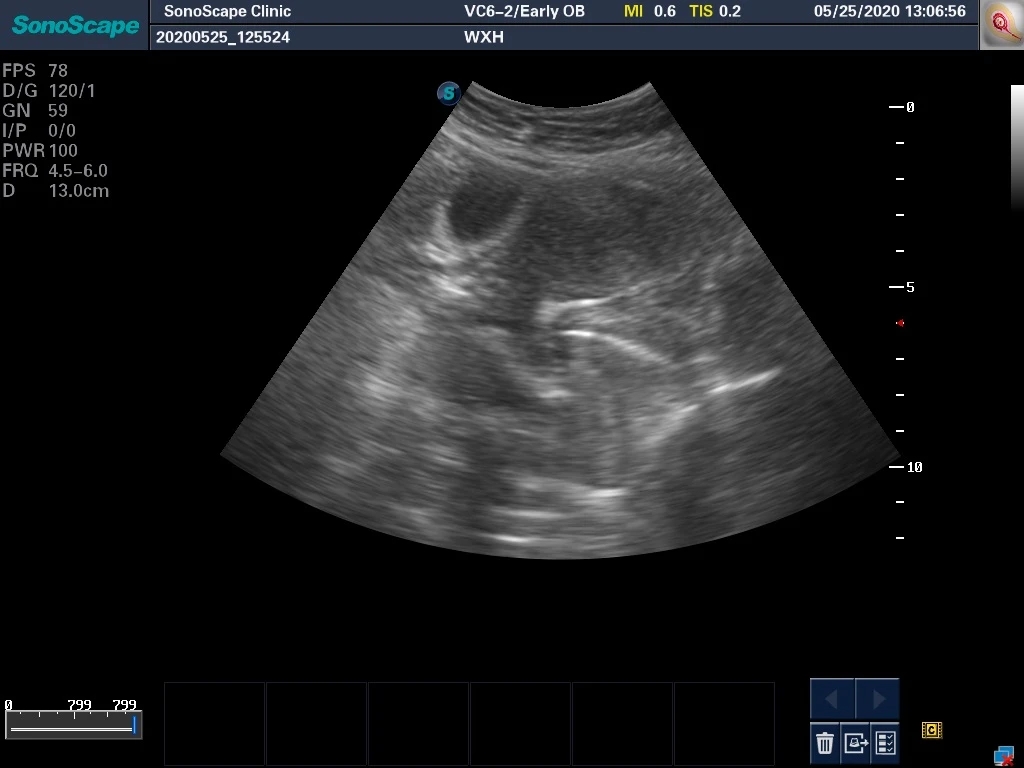

本例患者是“既往胎停后继发不孕,试管婴儿助孕后再次胎停后2个月月经不复潮”来诊,使用孕激素后月经有来潮,但月经量显著减少,彩超检查发现内膜薄。术前外院彩超没有电子版,在这里直接提供一份手术开始前的超声所见。

在上面这个图片中,我们可以大约看到子宫的轮廓以及微弱的内膜回声,标注呈现如下图: